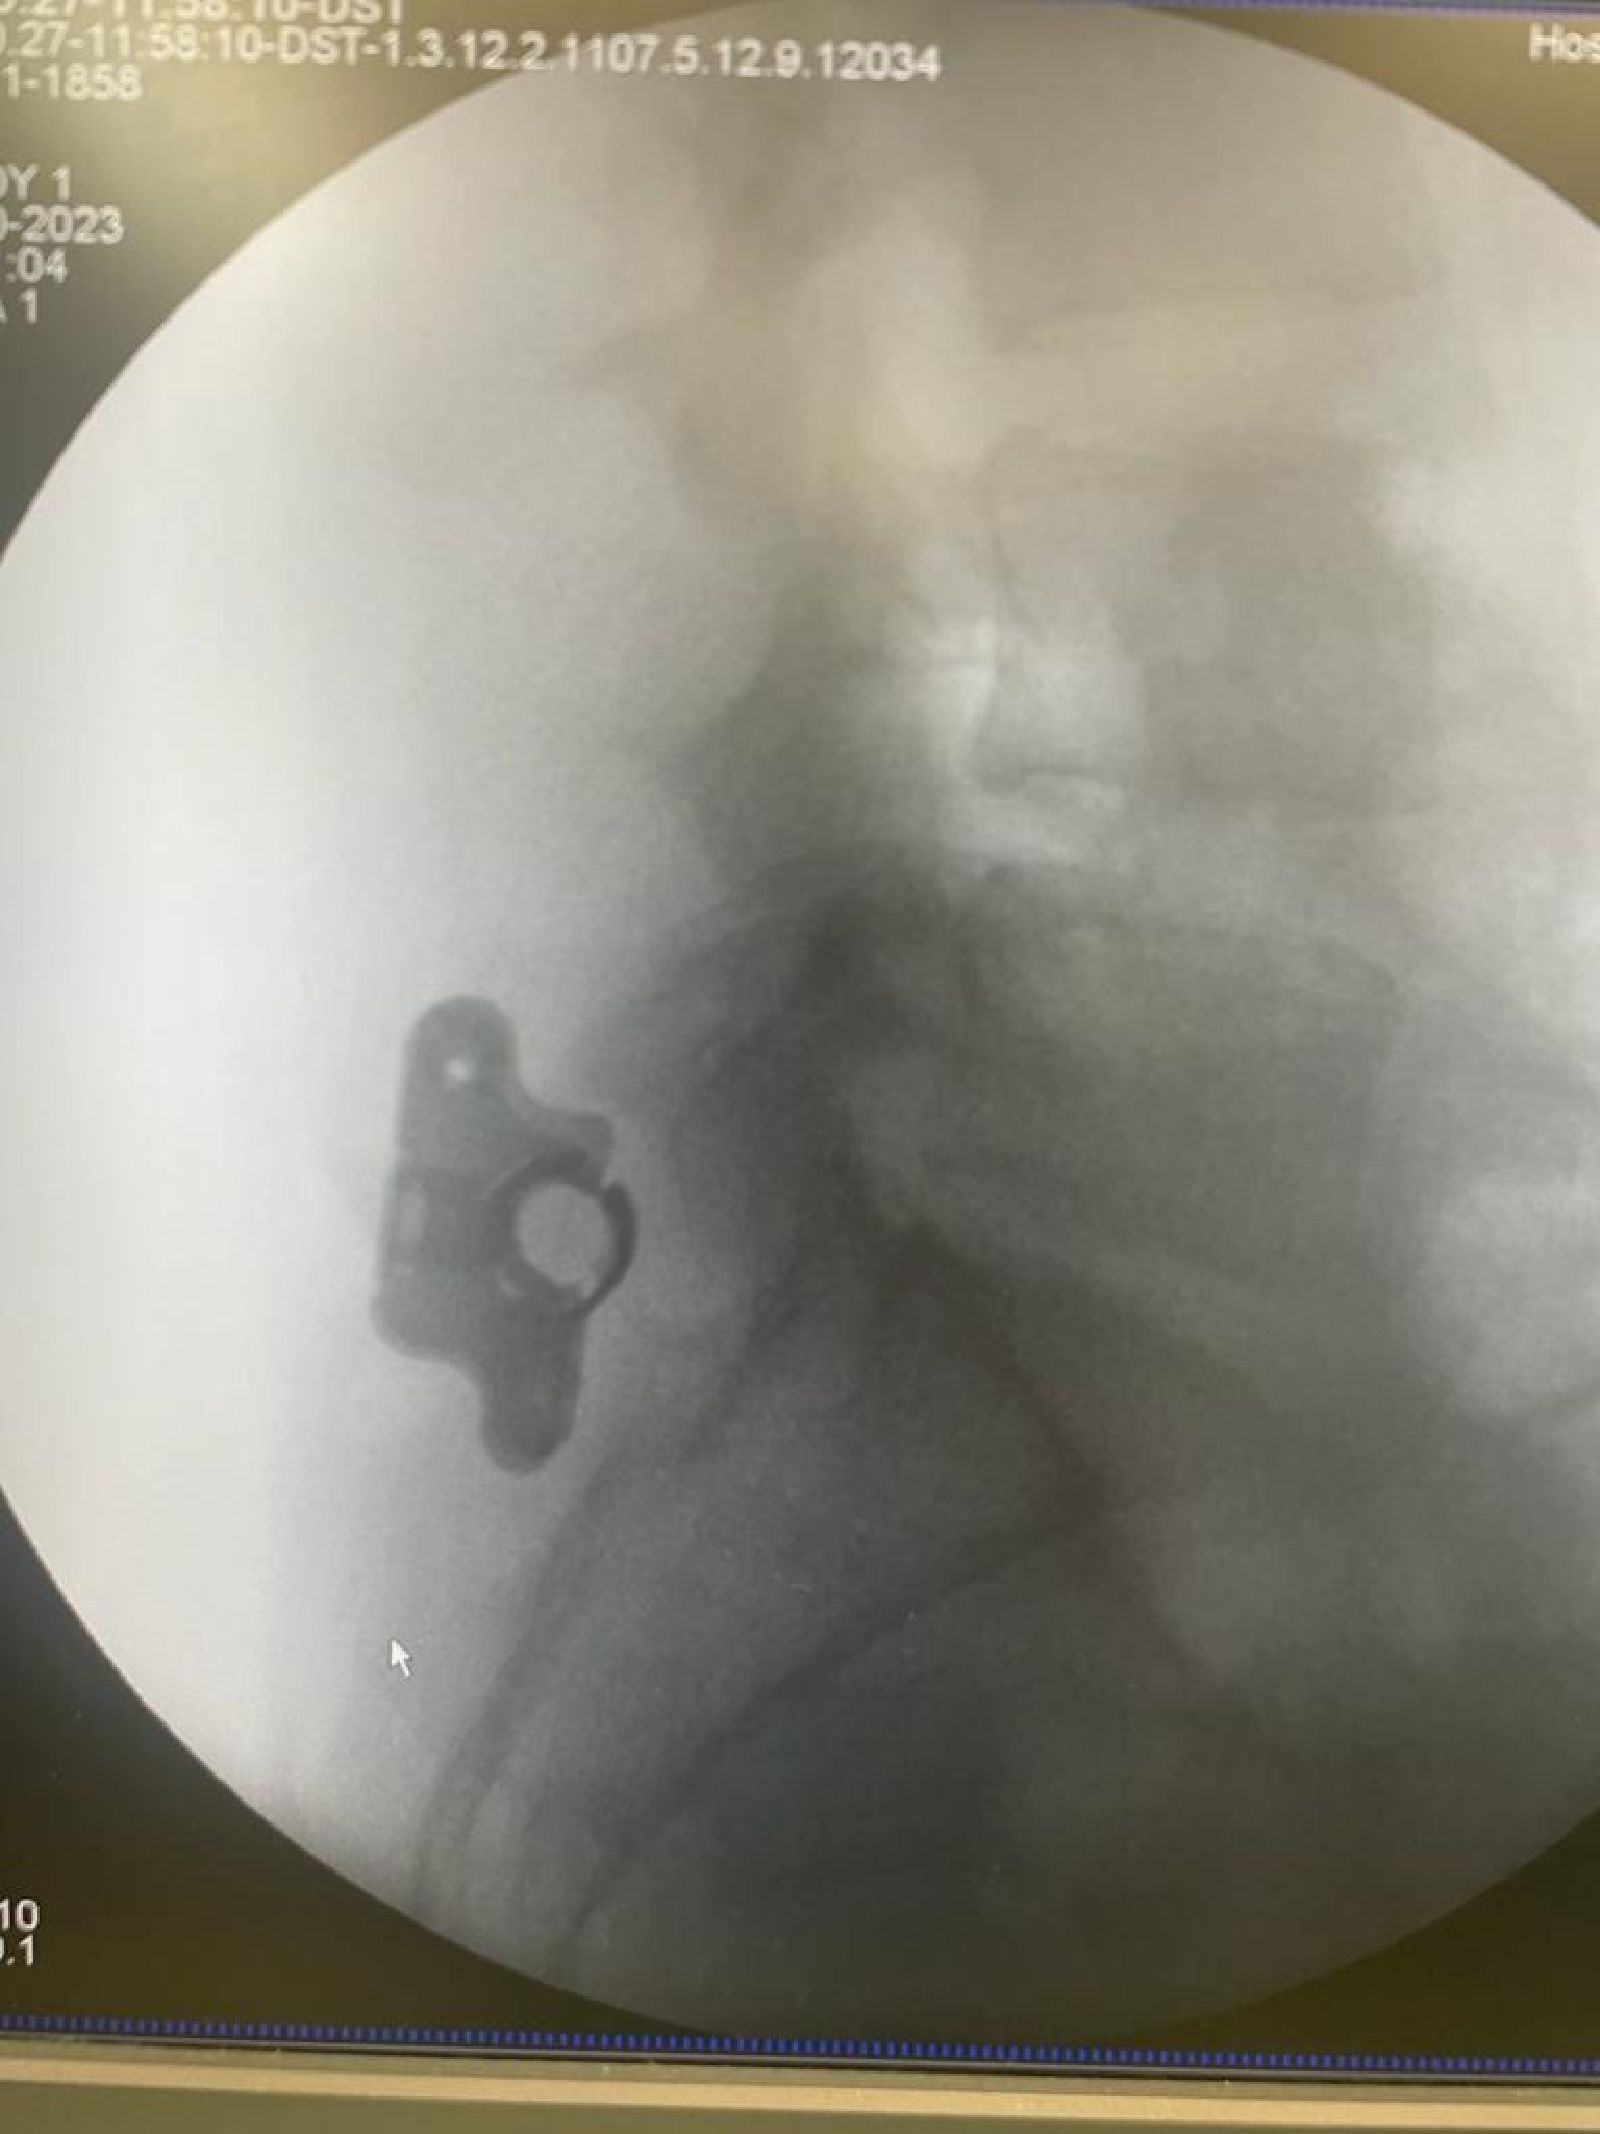

Patologia Degenerativa da Coluna Vertebral

- Tratamento de doenças que afetam a estrutura e função da coluna, com potencial impacto na qualidade de vida.